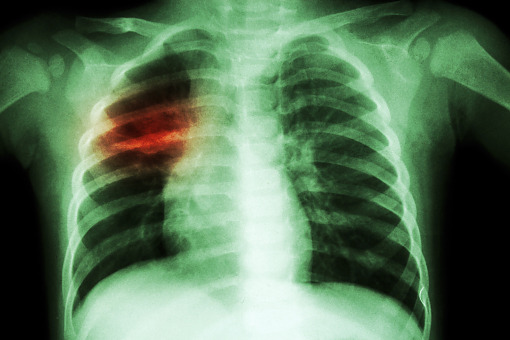

Sytuacja epidemiologiczna, jeżeli chodzi o nowe zachorowania na gruźlicę, utrzymuje się na...

W Światowym Dniu Gruźlicy, który przypada na 24 marca, główny inspektor sanitarny Paweł...

Pacjentom ze zdiagnozowaną gruźlicą przysługują darmowe leki. Nie wszystkie podmioty medyczne...